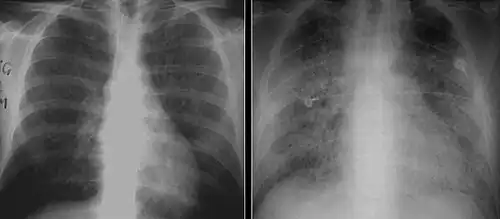

The diagnosis can be confirmed by the characteristic appearance of the chest X-ray and an arterial oxygen level (PaO2) that is strikingly lower than would be expected from symptoms. Gallium 67 scans are also useful in the diagnosis. They are abnormal in about 90% of cases and are often positive before the chest X-ray becomes abnormal. Chest X-ray typically shows widespread pulmonary infiltrates. CT scan may show pulmonary cysts (not to be confused with the cyst-forms of the pathogen).

These chest radiographs are of two patients. Both show ground glass opacities. The left X-ray shows a much more subtle ground-glass appearance while the right X-ray shows a much more gross ground-glass appearance mimicking pulmonary edema.[7] -